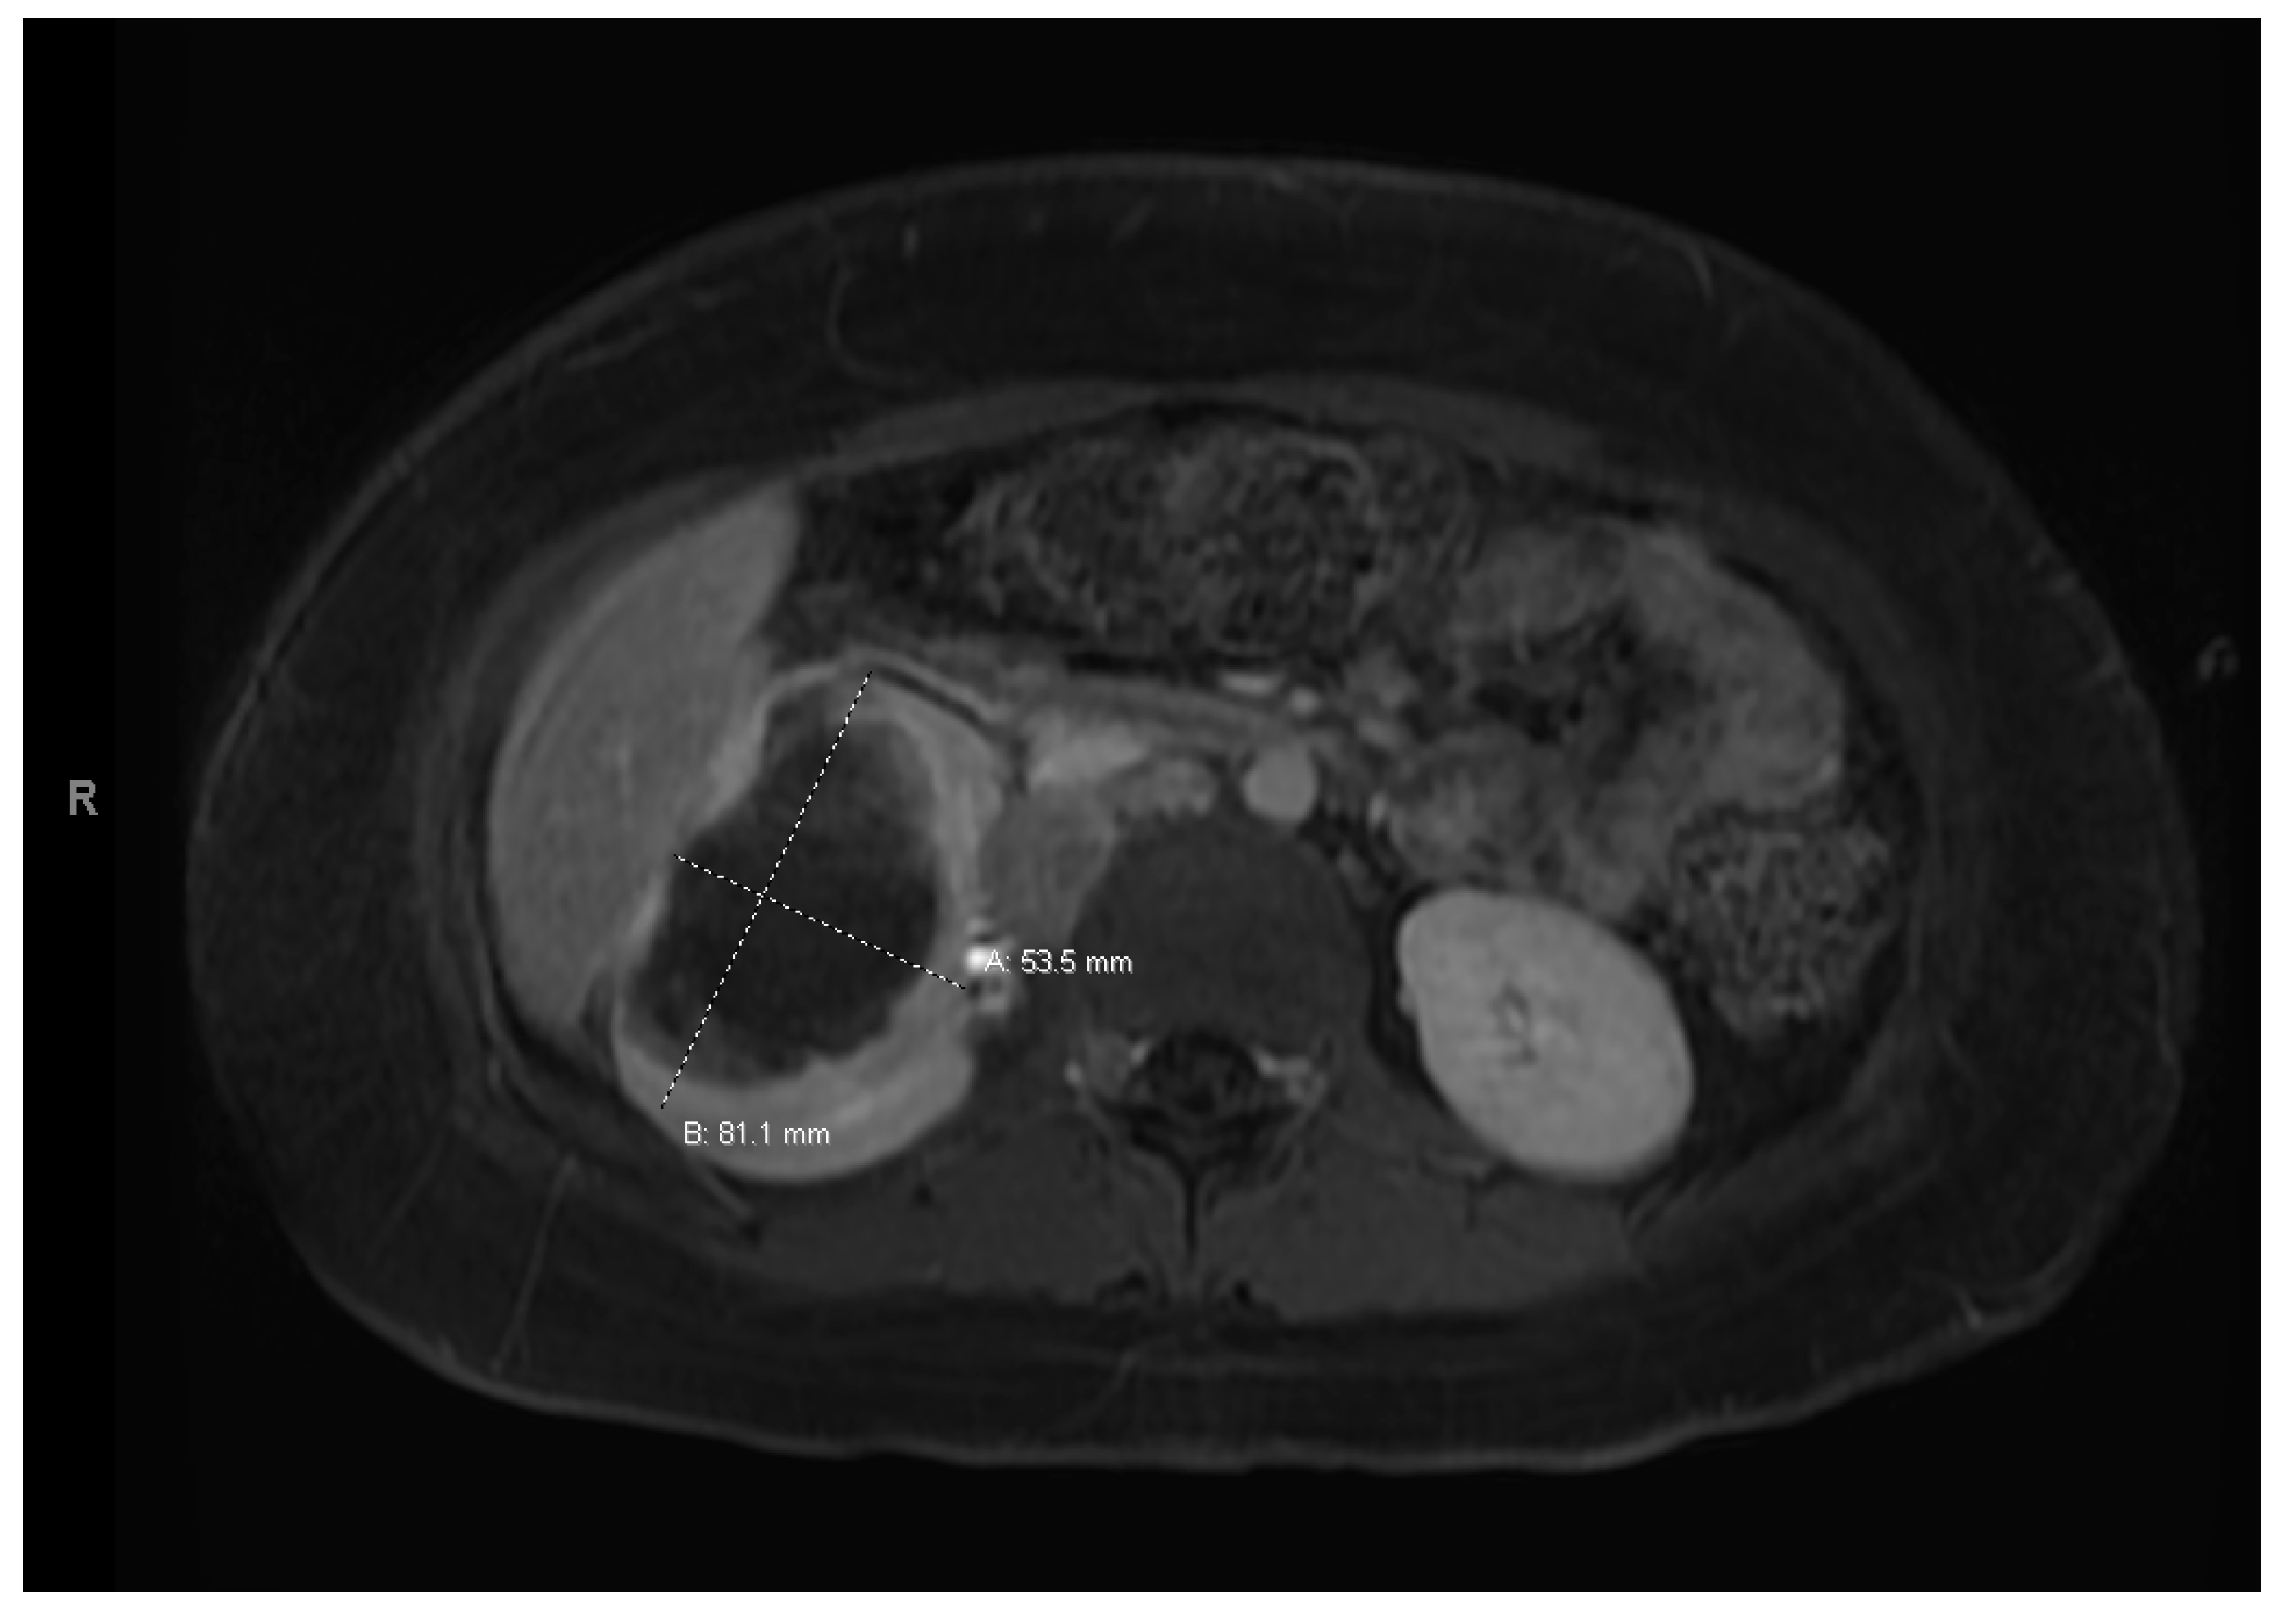

At age 15, she presented to an outside ER with a 2–3-day history of worsening right lower quadrant abdominal pain, nausea and occasional vomiting. She also had a history of a 20-lb weight loss over the past few months due to decreased appetite. CT scan showed a right renal mass 7 cm in size. She was transferred to our hospital and MRI abdomen/pelvis showed an indeterminate left adrenal nodule (Figure 3) and a large, solid, peripherally enhancing right renal mass with central heterogeneity measuring 8.1 × 5.4 × 8.7 cm (Figure 4). It also showed retroperitoneal lymphadenopathy with a retrocaval node at 4.1 × 2 cm, superior retrocaval node at 2.6 × 1.6 cm and an inferior precaval/aortocaval node at 1.5 × 0.9 cm. There was also a right lung nodule noted on a chest CT (Figure 5). She then had a baseline positive emission tomography (PET) scan which again showed the right renal mass, concerning for primary renal cell carcinoma, FDG avid retroperitoneal lymphadenopathy, concerning for metastasis and small bilateral pulmonary nodules, concerning for metastasis. She underwent a biopsy of the right renal mass, which was inconclusive. She underwent a second biopsy and was found to have RCCU-MP manifesting as a high-grade malignancy with loss of SMARCB1 by immunohistochemistry in the absence of a sickle hemoglobinopathy.

Figure 3. Left adrenal nodule.

Figure 4. Right renal tumor.